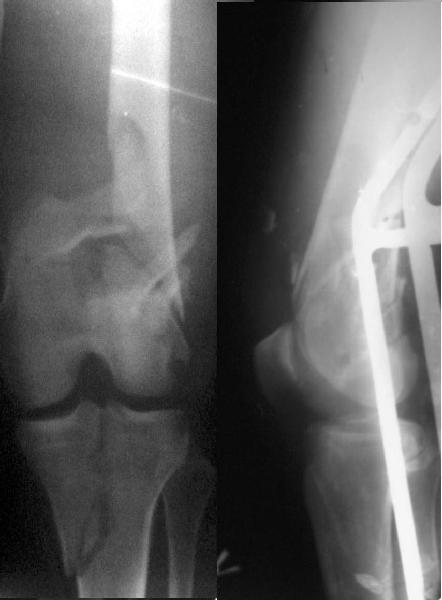

Re: Open supracondylar femur fx

Zsolt Balogh 31 Октябрь 2004, 12:13

This is what we have done... As generally true for LISS look at the bone not the hardware.

There are two more srews above. The one not completely in got damaged head.